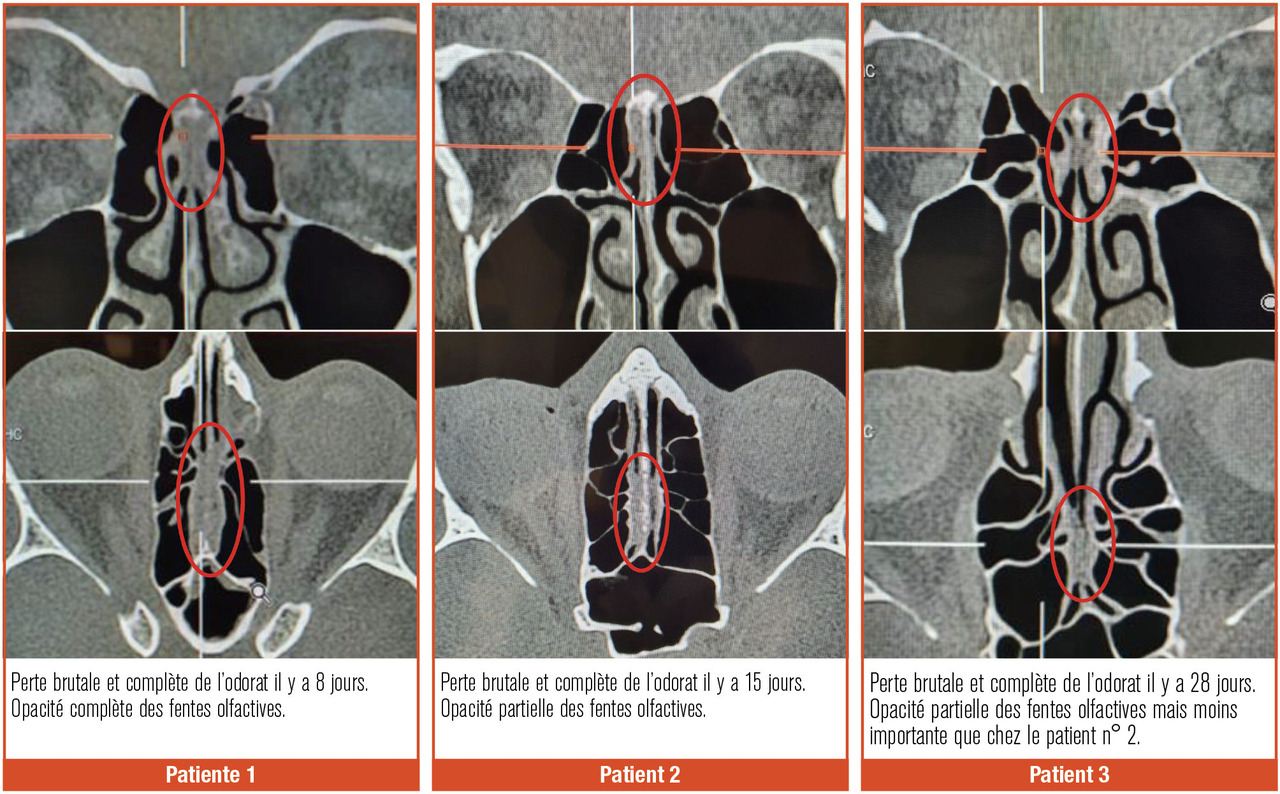

L’inflammation/destruction de la muqueuse olfactive est objectivée sur la tomodensitométrie et l’imagerie par résonance magnétique (IRM) nasosinusiennes. On observe, pendant la phase aiguë, des opacités complètes ou quasiment complètes des récessus olfactifs chez les patients Covid-19 ayant une perte brutale de l’odorat (fig. 2 ). Ces anomalies sont souvent isolées, sans atteinte des sinus paranasaux ni des cavités nasales. Ces opacités diminuent ou disparaissent au fil du temps lorsque les patients ont récupéré totalement leur odorat.